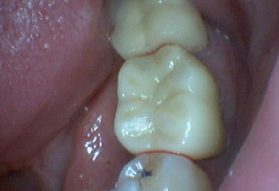

Zirconia Bruxir Crows, Cuspal Fracture